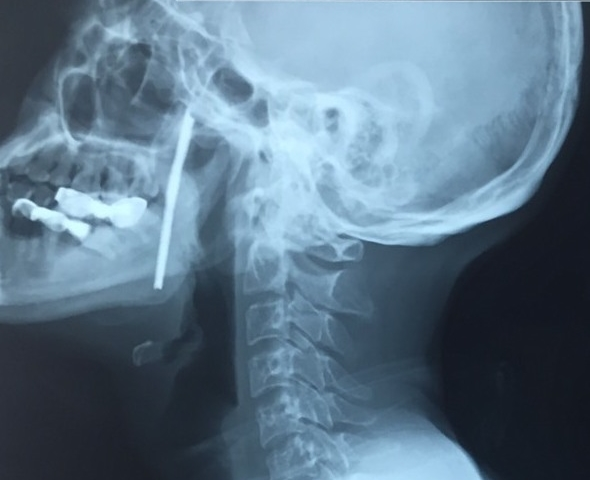

Hình ảnh phim chụp X-quang của bệnh nhân.

TS. BS Vũ Ngọc Tú - Trung tâm Phẫu thuật Tim mạch và Lồng ngực, Bệnh viện Hữu nghị Việt Đức cho biết, người bệnh được chẩn đoán vết thương phức tạp vùng cổ, do dị vật kim loại dài, xiên từ hầu họng vào trong miệng. Đây là vùng có rất nhiều cơ quan hệ trọng của cơ thể như đường thở (khí quản), đường ăn (thực quản), các mạch máu nuôi não (động mạch cảnh) ...